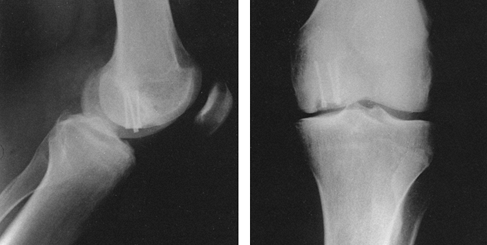

![]() |

Figure 11.22. A:

Comminuted proximal tibial fracture in an elderly patient, showing a combination of external and internal fixation to stabilize the comminuted periarticular fracture pattern in an osteopenic patient. B: Radiotranslucent carbon fiber rods facilitate assessment of the fracture site and proper timing of secondary intervention, yet provide sufficient stability to allow for soft-tissue consolidation. |